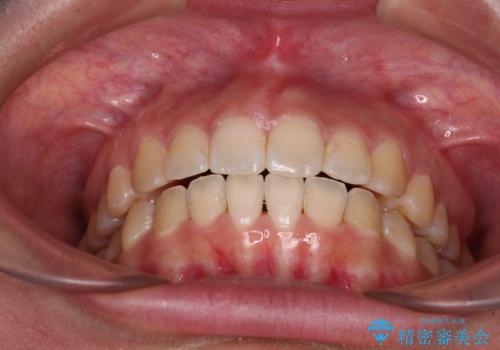

- 上下の前歯が非接触であることと、それに伴う口元の閉じにくさを気にして来院された患者様です。

奥歯の咬み合わせを見ると、上顎が下顎に対して相対的に前方にありました。

口元の閉じにくさを改善するためには、上顎臼歯を後方に移動させた咬み合わせにする必要があります。

インビザライン単体で改善することも可能ですが、達成する可能性が高くないため、カリエールディスタライザーという補助装置を併用して、より確実性を上げることとしました。

奥歯の咬み合わせを改善しながら、並行してインビザラインで歯列を整えることとしました。

カリエールディスタライザーを併用したことで、確実かつ短期間で治療を終えることができました。